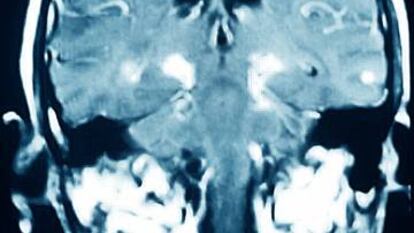

¿Son reversibles los daños cerebrales del párkinson?

El deterioro provocado por la enfermedad no se puede revertir aunque, durante un tiempo, sus síntomas se pueden corregir con tratamientos